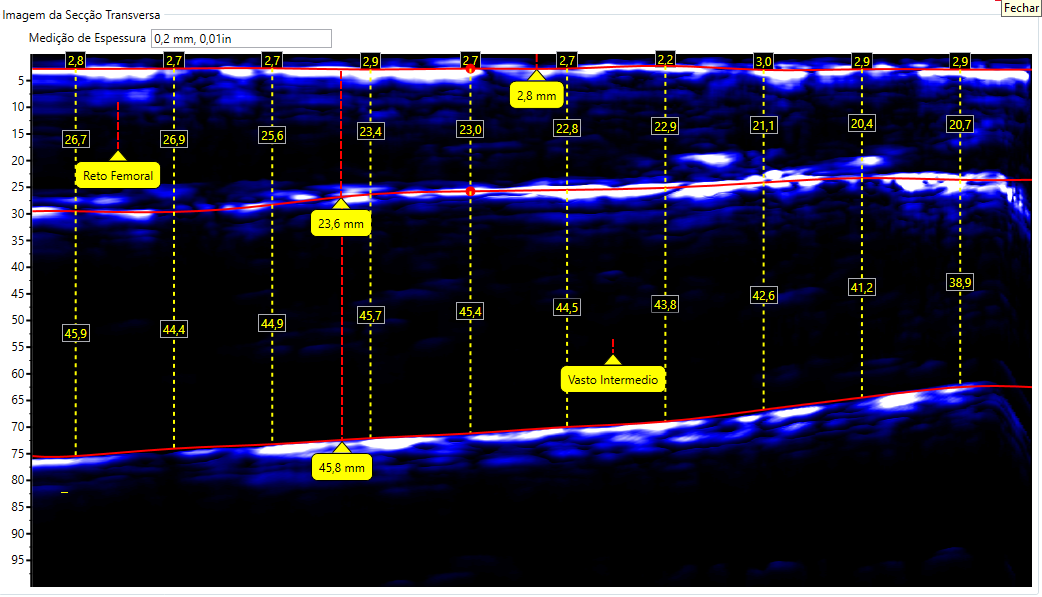

Escaneamento da Coxa